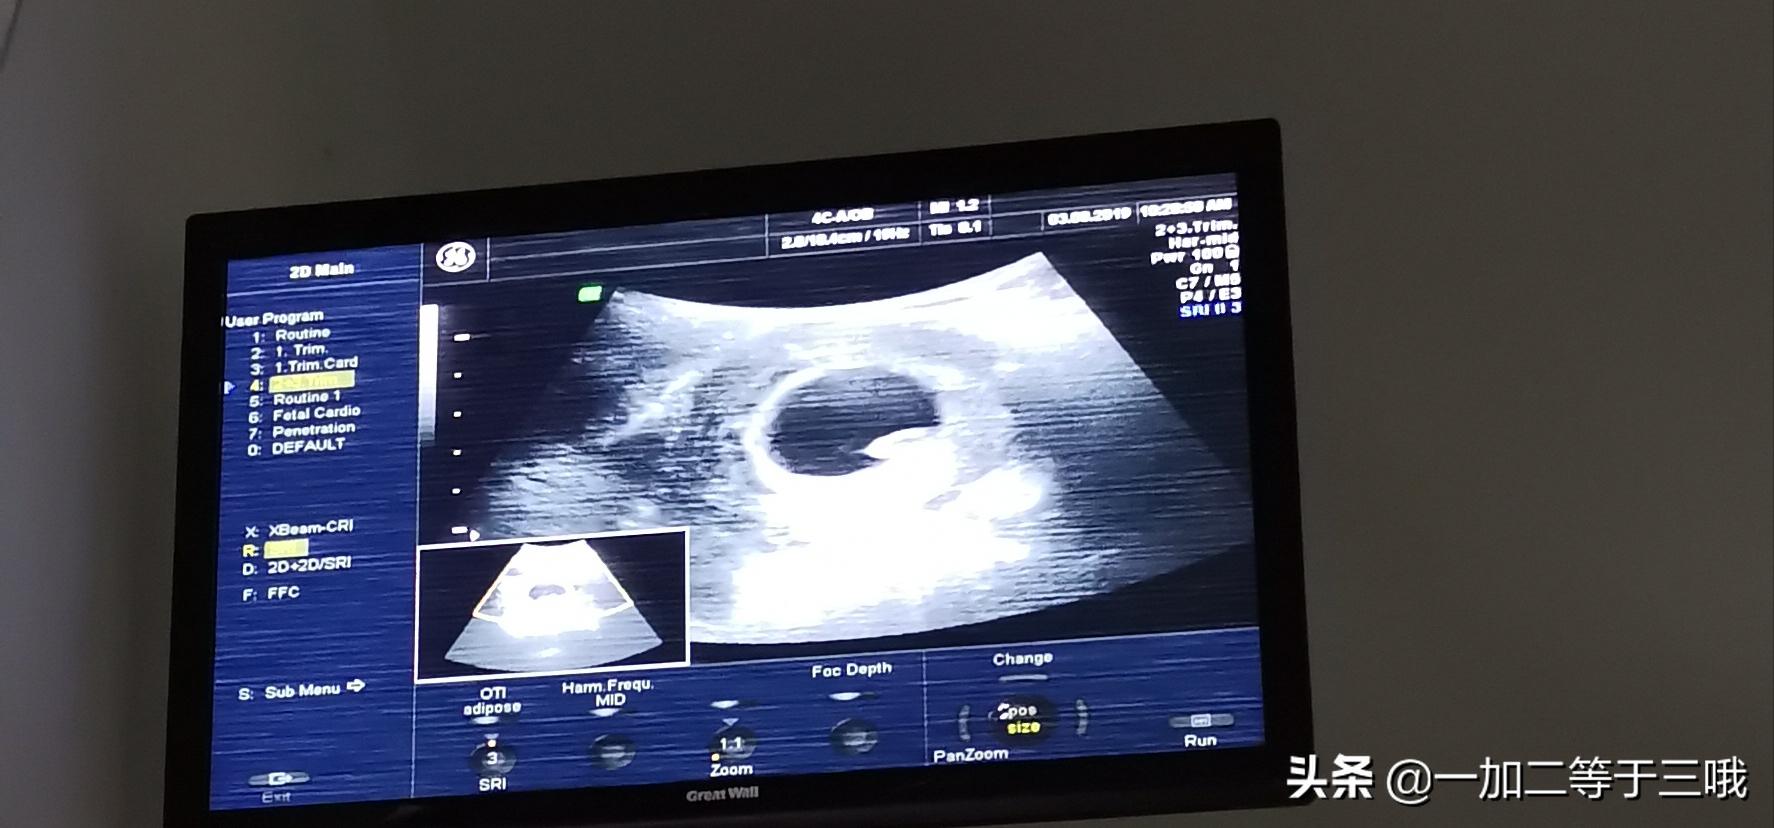

三个月一晃而过,身体没有任何不适。第一次产检时间到了。真的是一朝被蛇咬十年怕井绳,感觉走到医院已经用尽了全身力气;挂号、缴费、排队......;NT结果是1.5mm,结果正常,我心情非常激动,当场就抓着老公一个劲地摇,天知道这对于我来说意味着什么!第一关过了,接下来的局势仍不容乐观。因为有一次不良孕史,所以我拒绝查唐筛、无创,直接预约孕18周检查的羊水穿刺。等待的时间异常顺利,很快就到了羊穿时间了,我们提前去做好术前检查,发现好多孕妈都要做,有高龄、不良孕史、唐筛无创异常等多种原因。我们相互讨论着,想在彼此身上寻求一点慰藉。

第一次产检